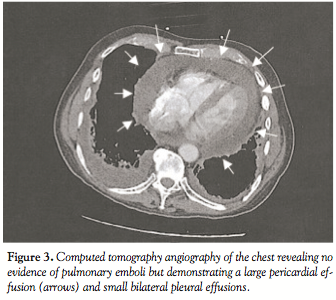

The patient was initiated on intravenous antibiotics with broad-spectrum coverage, fluid resuscitation with normal saline, and intravenous rate control with diltiazem infusion. Computed tomography angiography of the chest

revealed no evidence of pulmonary emboli, but demonstrated a large pericardial effusion and small bilateral pleural effusions (Figure 3). Bedside transthoracic echocardiogram confirmed the presence of a large circumferential pericardial effusion with diastolic collapse of the right ventricle (Figure 4) with marked respiratory variation of mitral and tricuspid inflow velocities, and plethora of the inferior vena cava verifying the clinical diagnosis of cardiac tamponade.